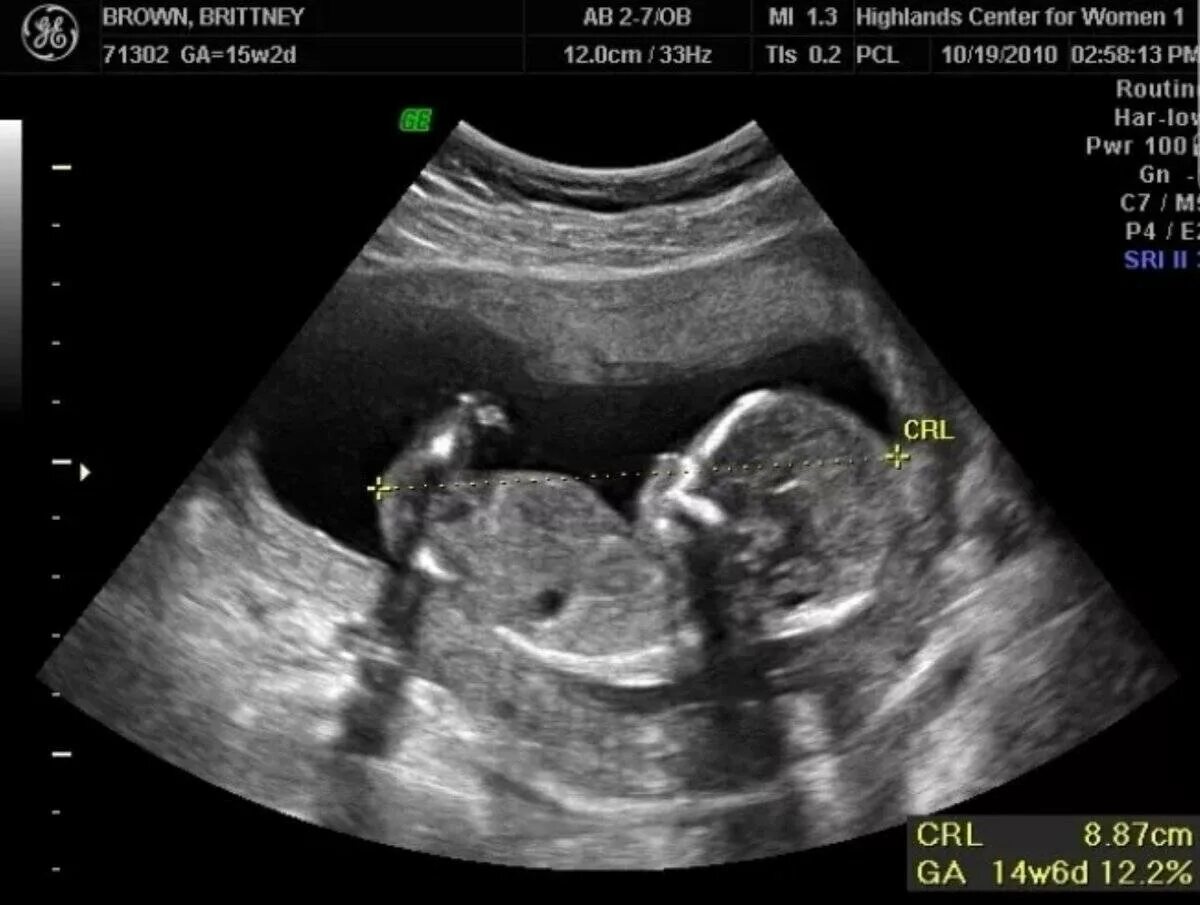

16 недель ощущения форум